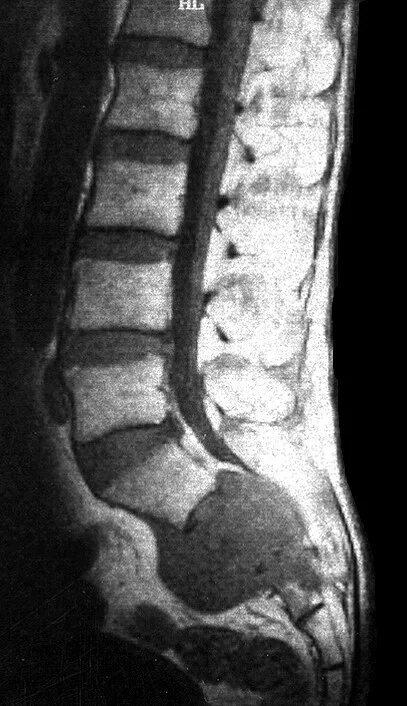

Метастазы в поясничном позвоночнике